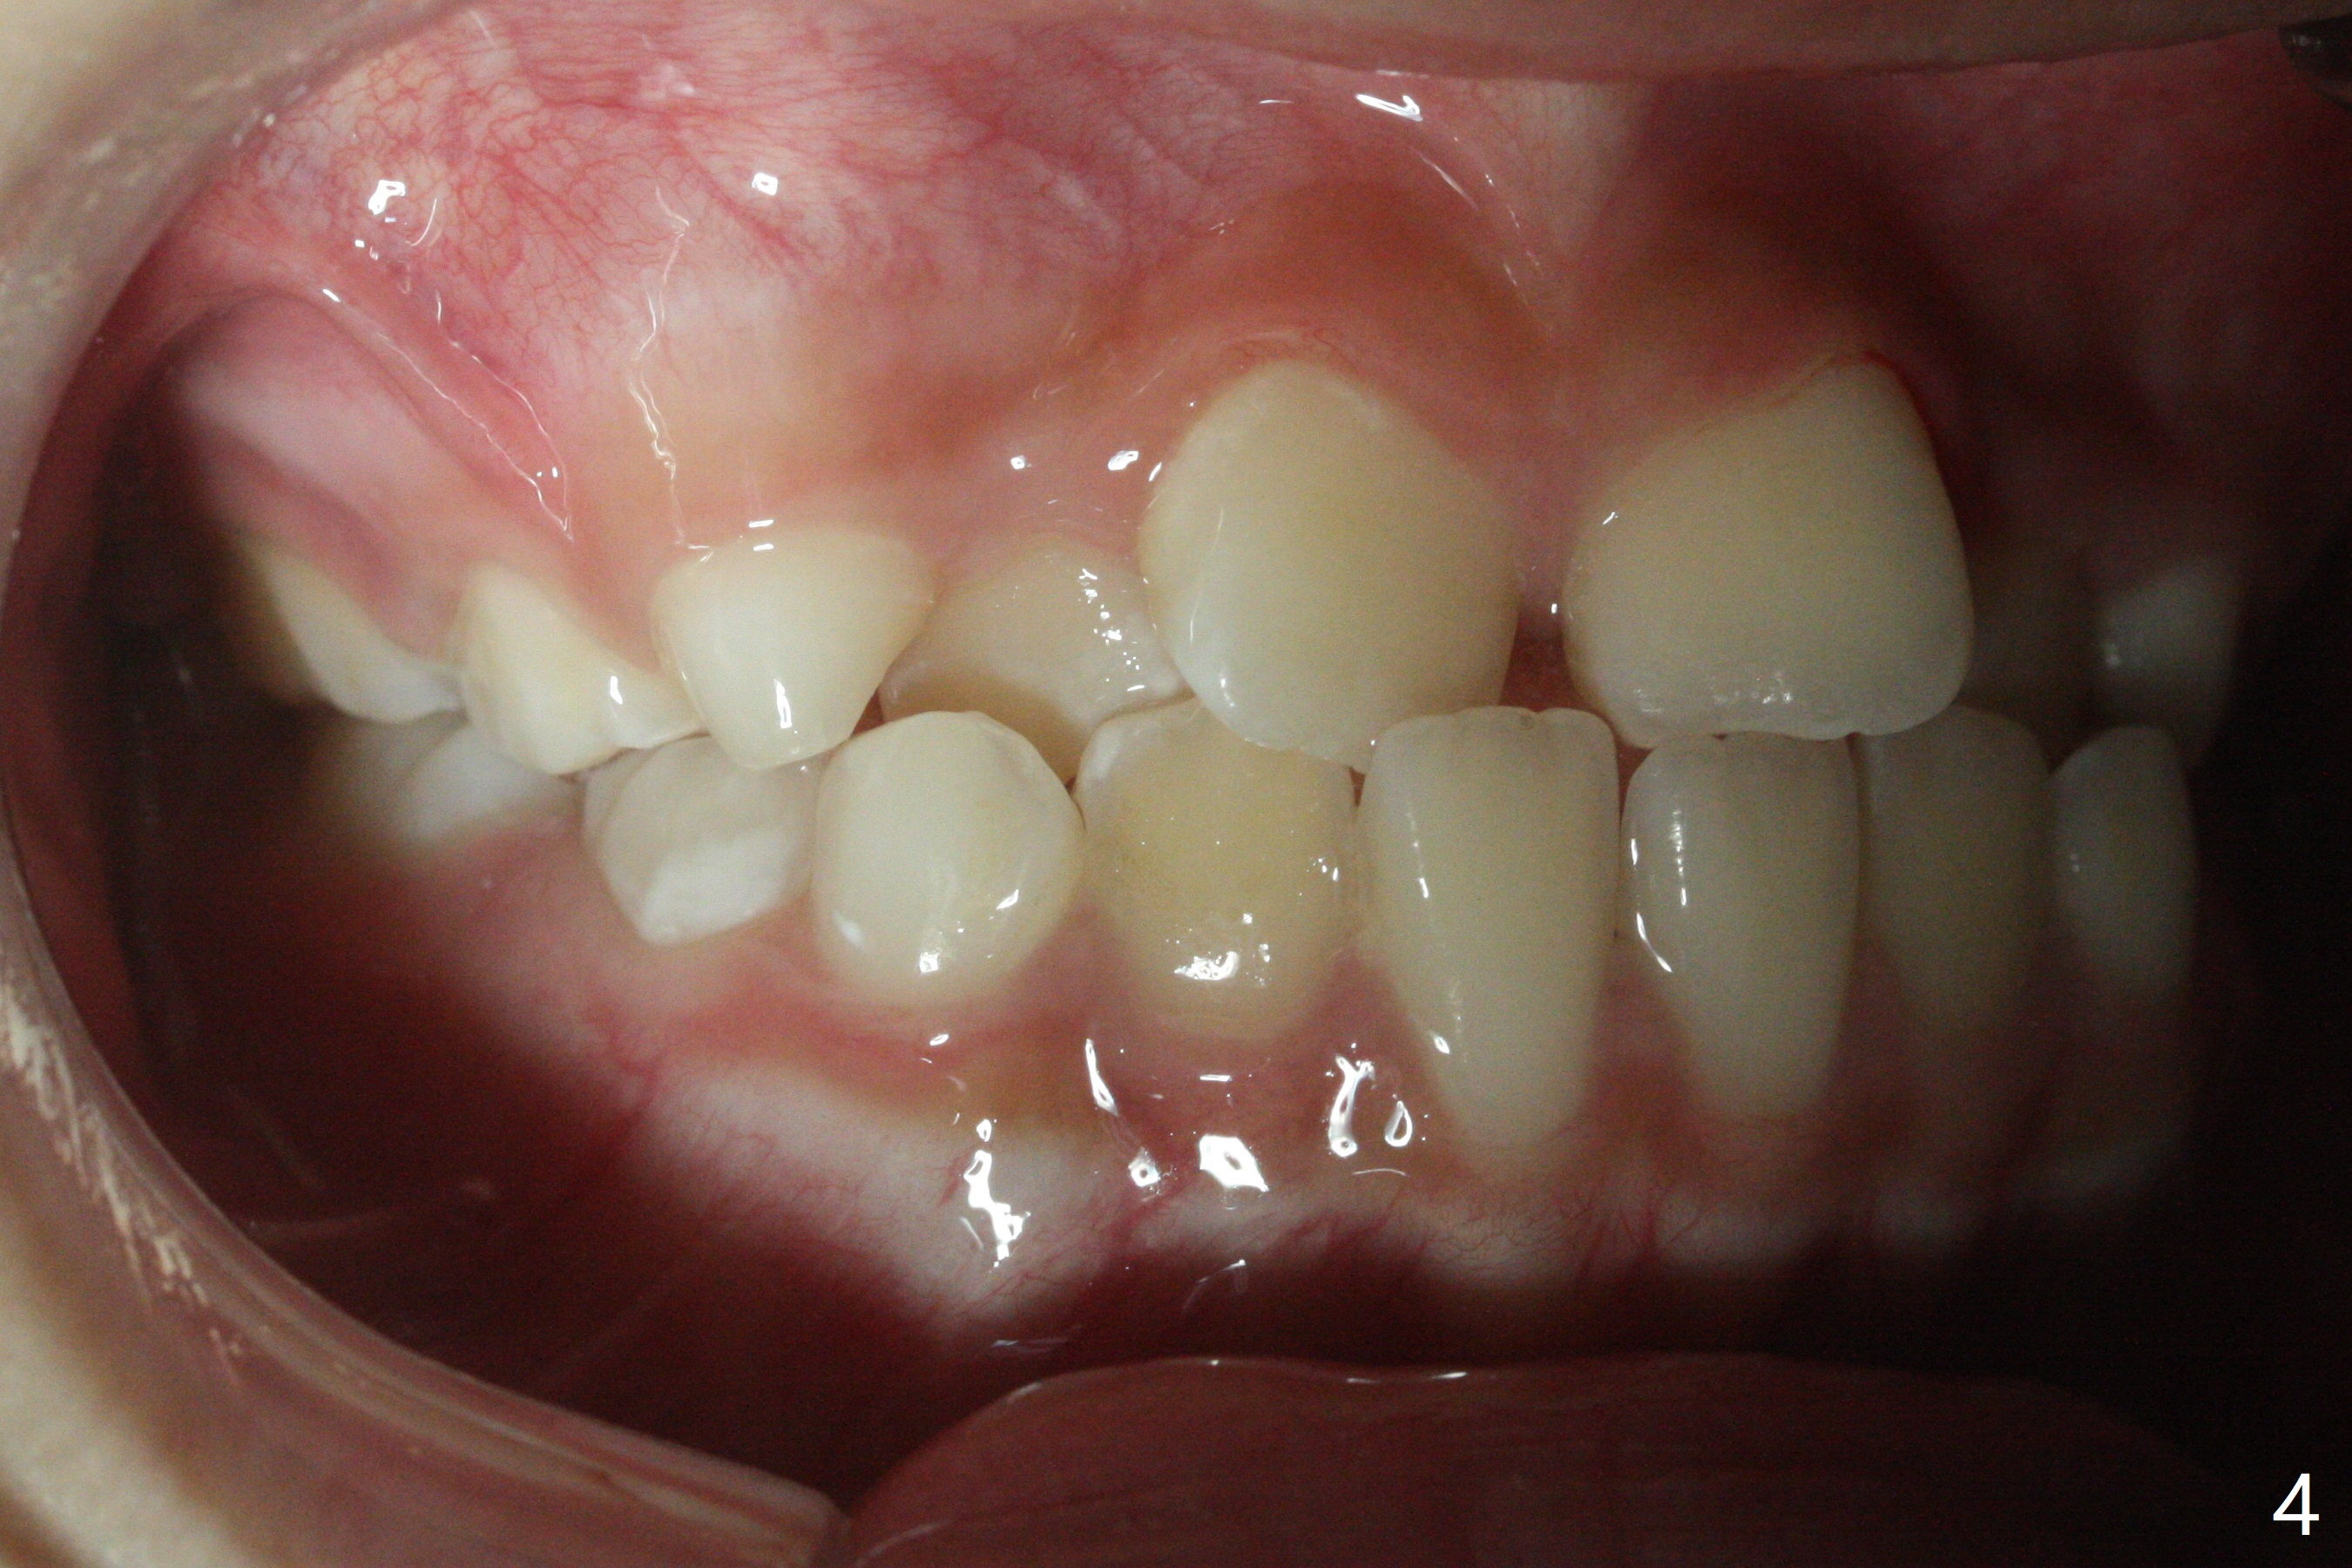

7岁女孩龋齿(图一)到八岁发展的严重(图二,三 (D))。为了有完整支抗,利用树脂(而不是不锈钢牙冠)保留左上第一乳磨牙(图六:D),以后可以安置矫正器。面部匀称(图七至十)。乳尖牙,第一恒磨牙:第一类咬合(图十一,十二)。左上前牙拥挤比右边轻,因为左上D龋齿破坏(图十三:D)。前牙扩弓时,右上D近中需要片切(^)。下颌拥挤轻(图十四),矫正器可以迟放置。